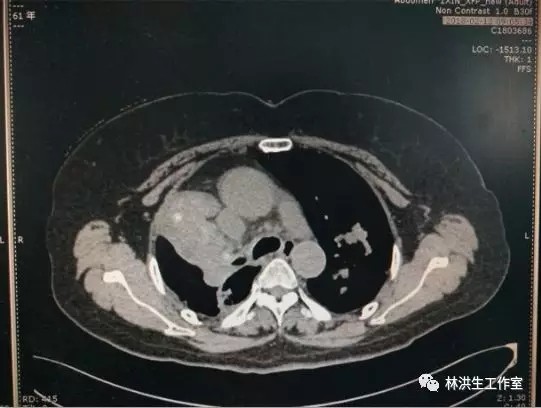

【诊断】右肺上叶癌 双肺多发转移 脑转移 IV期

【现病史】患者2013年4月诊断右肺低分化腺癌(7.4*5.6cm),双肺多发转移,基因检测:EGFR(-)。行培美曲塞+奈达铂方案4次化疗及氩氦刀治疗后肿物缩小(5.5*4.8cm),疗后评价:缩小SD。中西医结合至今,病灶进展缓慢,体力评分PS100分。

2013-8中药治疗前:右肺肿物6.5*5.2cm

2016-2中药治疗后:右肺肿物4.0*3.5cm